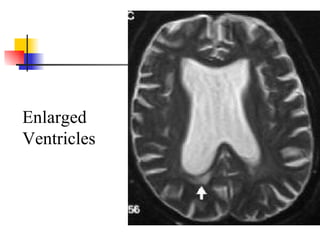

Diagnostic studies Ventricle enlargement on CT or MRI Severity graded by ratio of maximal frontal horn width divided by transverse inner diameter of skull 0.32 minimal for NPH but 0.40 more typical Lack of hippocampus or cortical atrophy Periventricular and cortical white matter lesions may be found in patients with NPH Large number white matter lesions may be marker for poor response to shunting

Enlarged Ventricles